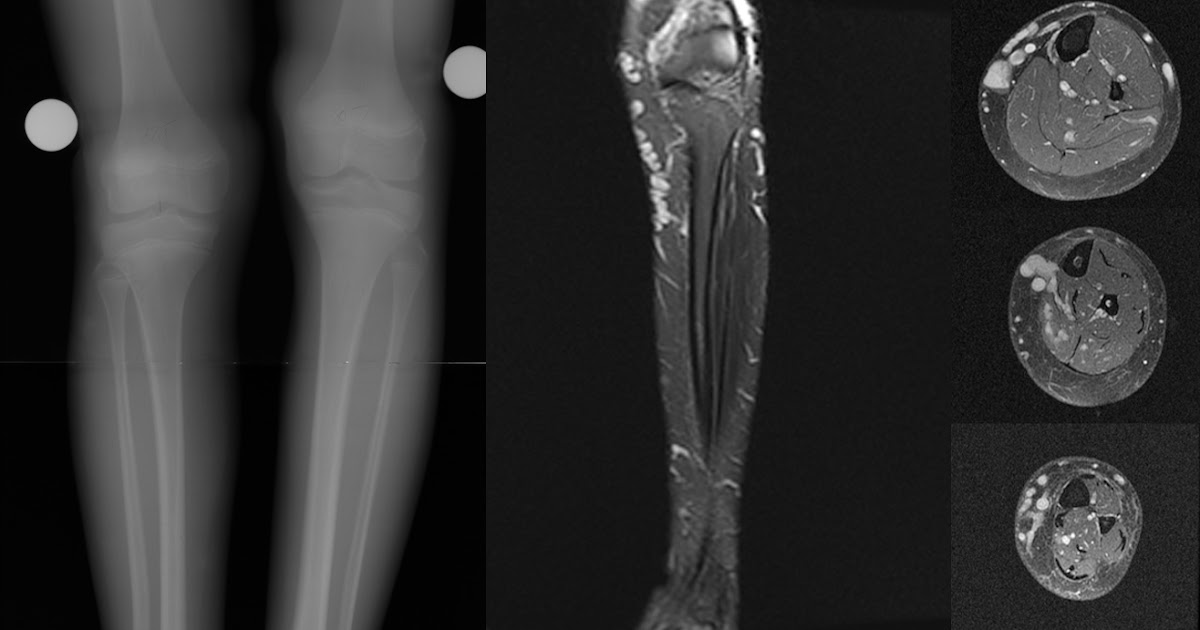

Синдром паркса вебера рубашова

Синдром паркса вебера рубашова 119 фотографий